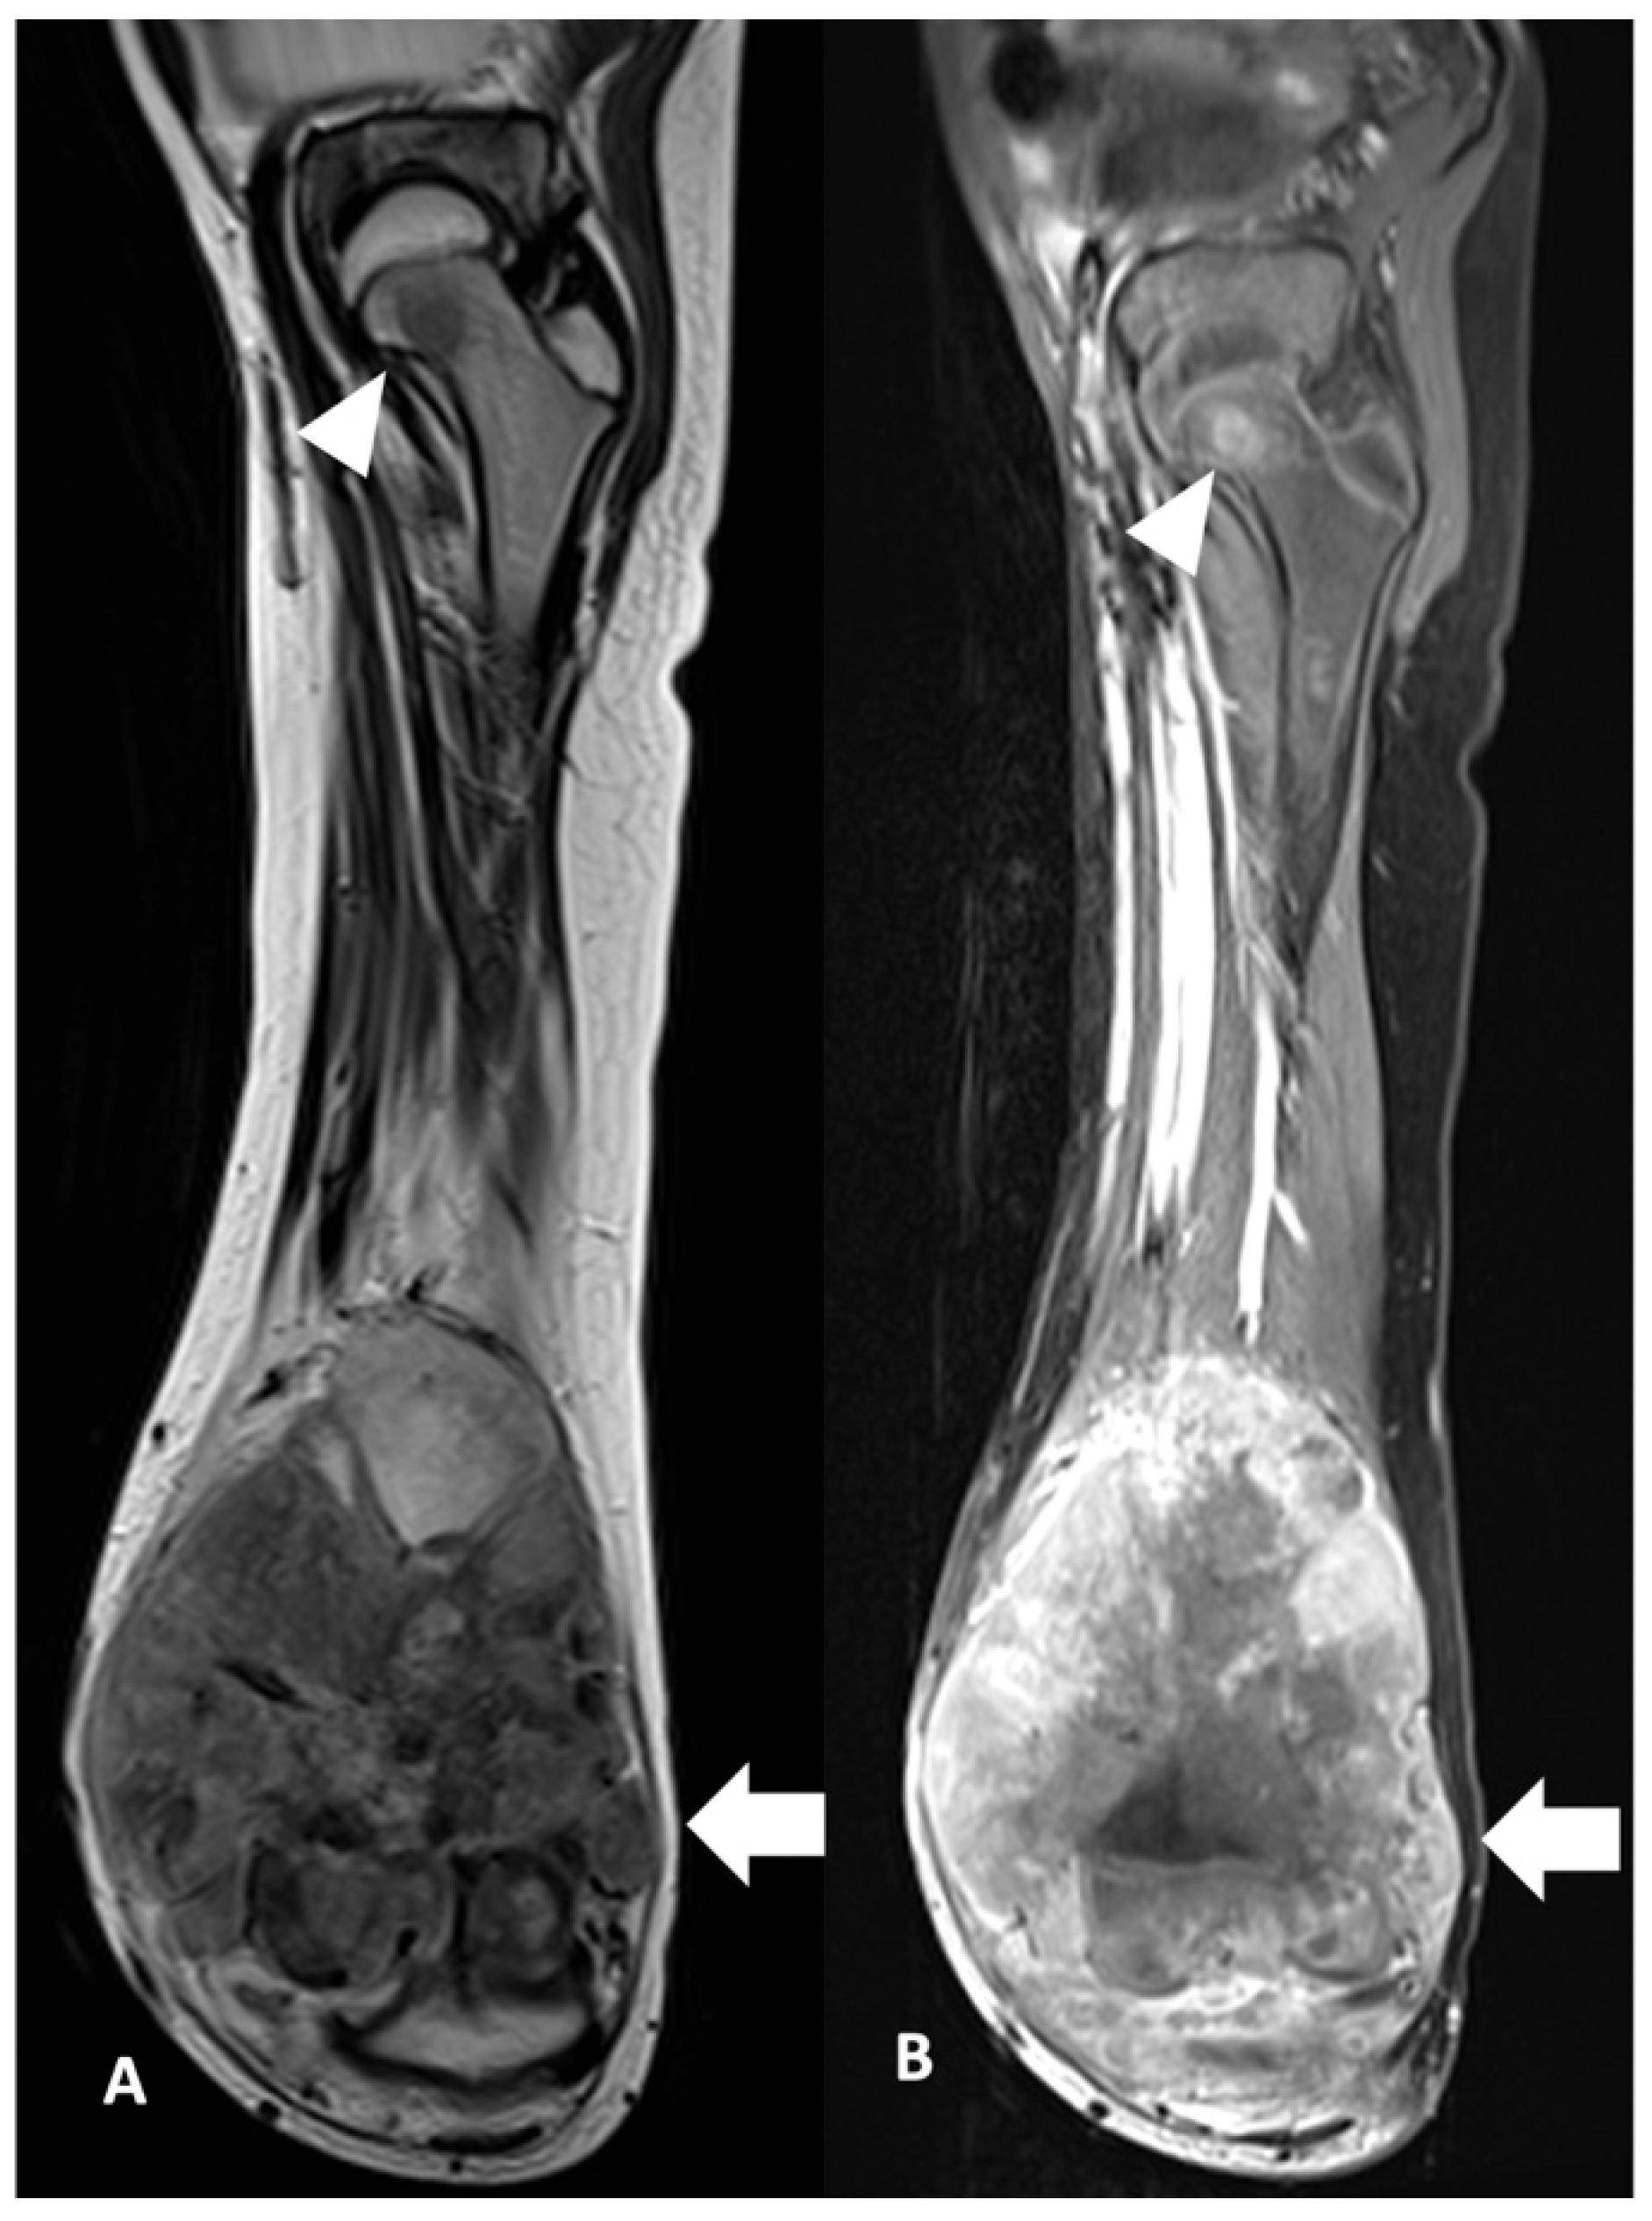

| Skip Metastasis | Presence | 0 (0.0%) | 5 (100.0%) | 0.041 * |

| Absence | 14 (60.9%) | 9 (39.1%) | ||